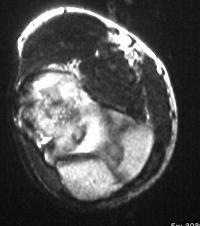

MRI shows an osteochondral sequestrum of the anterior capitellum:

Treatment options? Do nothing, Open reduction and bone graft, sequestrum excision or radial head excision. In this case, at surgery, the loose articular fragment was too thin to allow reliable fixation, and was simply excised.